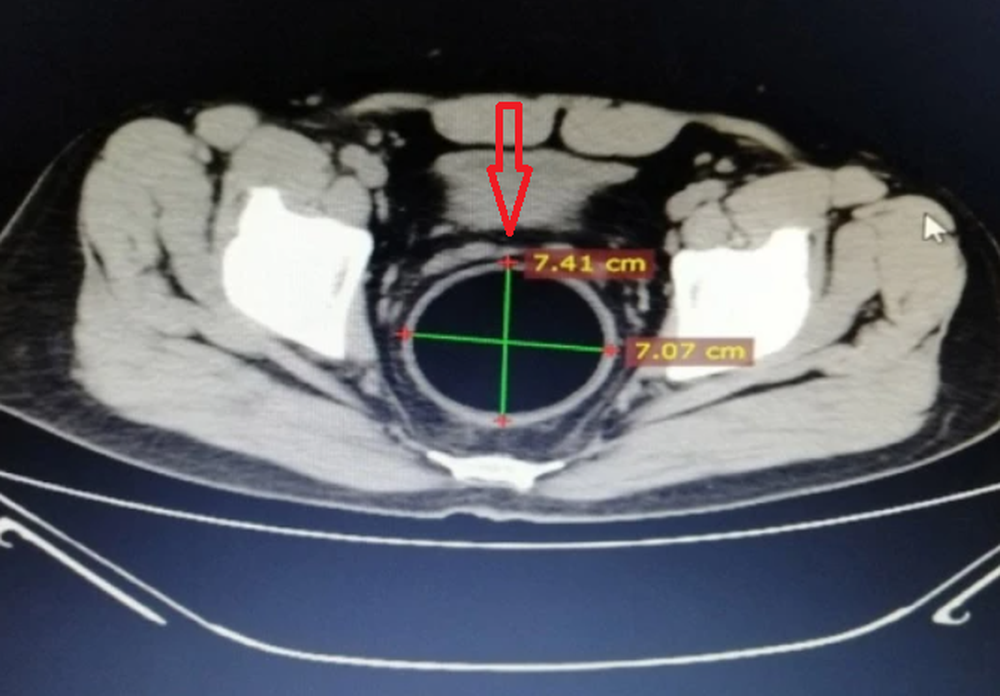

Ảnh chụp cắt lớp cho thấy quả bóng lớn có đường kính khoảng 7-8cm

Các bác sĩ thăm khám cho biết bệnh nhân có sức khoẻ ổn định, tinh thần hợp tác và họ cũng phát hiện các vết xước xung quanh hậu môn. Bác sĩ đã sử dụng tia X và chụp cắt lớp phần bụng để xác định vị trí của dị vật, nhưng họ cũng chưa thể lấy nó ra ngay nên đã lên lịch phẫu thuật cho nam bệnh nhân vào sáng hôm sau.